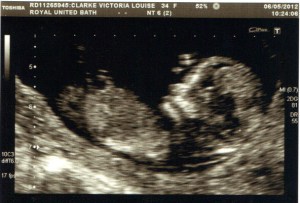

It was around 8 months ago that our whole world was turned upside down when this happened :-

So anyway getting to the hospital and getting the news that your baby is fit and healthy is an amazing feeling. And of course seeing what will eventually be your child is a pretty incredible moment in your life. The wonderment of an ultrasound scan is difficult to explain until you see it for yourself :-

The general concern for your babies health starts here and will probably never end even when they are the ones taking you out for dinner because you are too old to look after yourself.

The results from this scan are used to tell you of your risk of certain syndrome’s the main one being Downs syndrome. Our result returned as 1 in 290 which is considered to be low risk however it was a bit too close for comfort to the result that is considered high risk. For those of you that dont know the number is calculated based upon a number of tests, the main one being the length of the nuchal fold